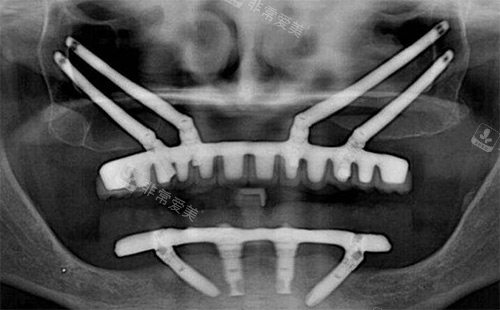

all-on-4种植适合哪些缺牙人群?

all-on-4种植技术是半口/全口缺牙人群的理想选择,牛凯医生通过这项技术帮助许多顾客实现“当天种牙当天用”。

半口/全口缺牙者:传统半口缺牙可能需要种8-10颗种植体,而all-on-4需要4颗种植体就能支撑半口牙齿,减少手术创伤和费用,适合年龄较大、不想多次手术的人群。

骨量中等不足者:通过倾斜种植体设计,利用现有骨量,避免植骨,尤其适合牙槽骨吸收较重度但不想植骨的顾客,牛凯医生会根据顾客骨密度定制倾斜角度,确保种植体稳定。

追求快速修复者:all-on-4支持即刻负重,手术当天就能戴上临时牙冠,不影响正常生活和社交,很多顾客反馈“上午种牙,下午就能吃软饭”,大大提升了生活质量。